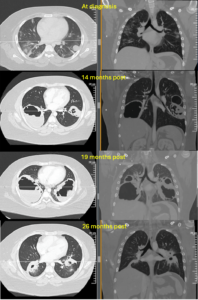

These images are of a 14-year-old boy diagnosed with PR3+ granulomatosis with polyangiitis. His disease manifested with bilateral iritis, vasculitic rash with chronic ulceration, sinus disease, arthritis, proteinuria and hemoptysis, with alveolar hemorrhage and nodules on both lungs.

From top: Figure 1 shows the evolution of very large pulmonary cavitary nodules, with computed tomography (CT) images of the chest taken at diagnosis, at disease flare, at failure of remission induction and at repeat induction. Figure 2 shows the sinus disease with edematous turbinates with copious discharge. Figure 3 is the CT scan of the sinuses, demonstrating perforation of the nasal septum and polypoid changes. Figure 4 depicts a chronic skin ulcer on the foot.